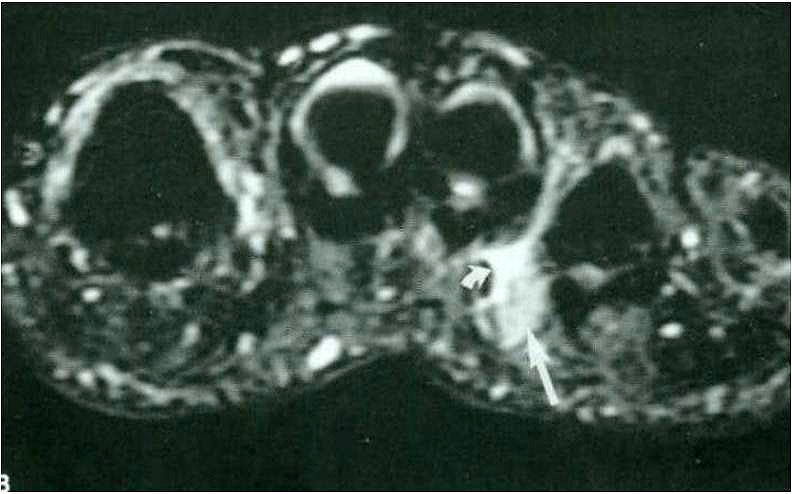

• MRT (in Bauchlage!) 7